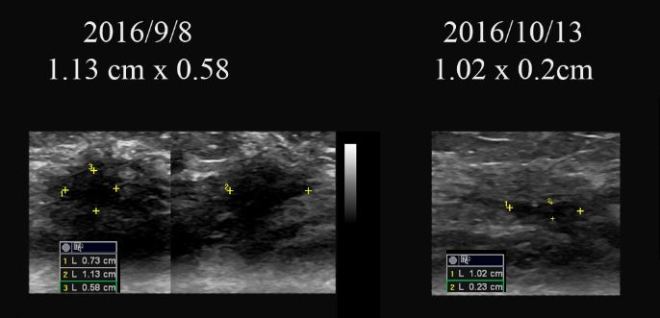

• 2015년 9월 유방암 발견  3.9 cm. 민간요법

• 2016년 2월 유방암 더욱 커짐  3.9cm  —-> 4.5 cm

• 2016년 3월 29일  본원 내원 종양  5cm 가량 약간 커졌음

• 2016년 4월 14일  본원  한약조치 이후  5cm의 종양  3.9 cm로 줄어들음

• 2016년 9월 8일  2.3cm(2016/5/26) —-> 1.13cm(2016/9/8)

• 2016년 10월 13일 약 10mm  x 2mm의 종양의 괴사된 흔적 남아 보임

• 2016 년 9월 8일    2.3cm(2016/5/26) —->  1.13cm(2016/9/8)

• 2016 년  10월 13일   약 10 mm  x 2 mm 의  종양의 괴사된 흔적 남아 보임.

이후 방사선이  끝나고  내원하여  9월 달  보니 종양의 거의 괴사되어서 1.13x  0.58 cm 의 크기가 남아 있었고  한달 뒤인  2016년 10월 13일에는  1.03 x 0.2cm 정도의 괴사된 흔적만 보였다.